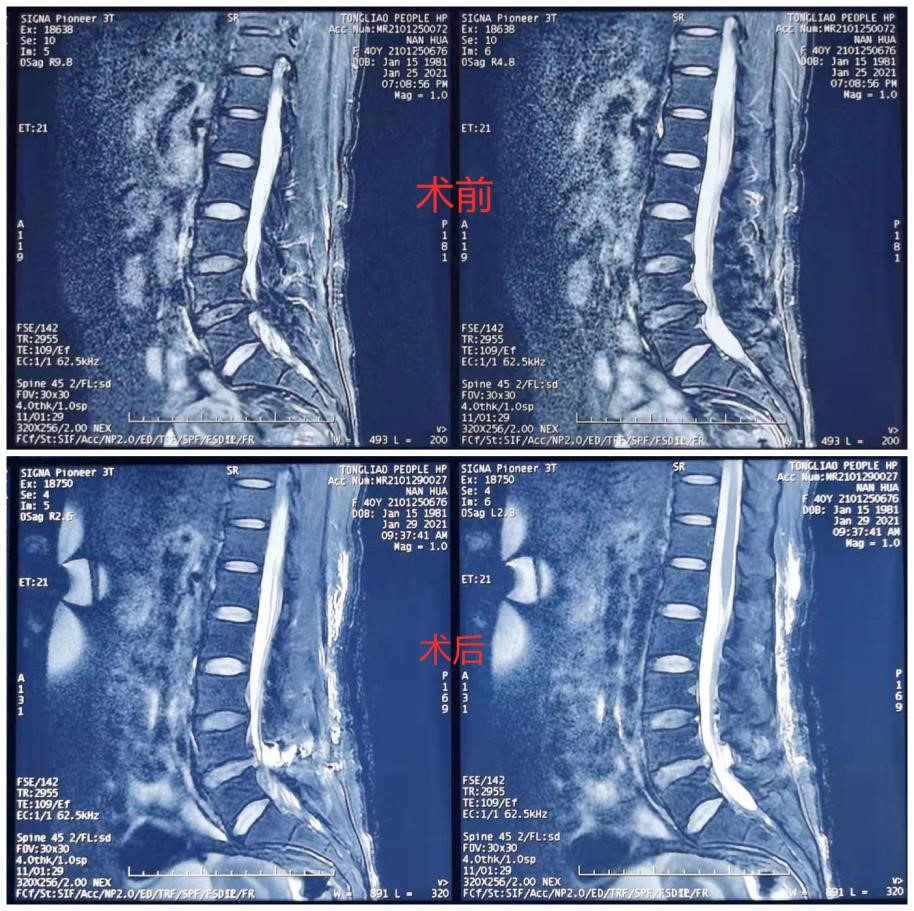

40岁的南女士有8年腰痛病史,自4月前开始,南女士时常会感受到右腿放射性疼痛、麻木。症状进一步加重,剧烈的痛感让南女士寸步难行,严重影响了她的日常生活与工作。带着巨大的病痛,南女士来到了我院骨四科就诊。查体显示南女士腰椎屈伸活动受限,右侧臀部肌肉较左侧萎缩,L3-4、L4-5、L5-S1椎体棘突叩击痛阳性,右侧臀部放射痛,双侧直腿抬高试验及加强试验阳性,右大腿后侧经小腿外侧至足外侧皮肤感觉减退、有麻木感;右侧踝及足趾背伸肌力下降。患者症状、体征与影像学表现相符,腰椎间盘突出伴椎管狭窄诊断明确。结合患者情况,我院骨四科燕飞主任决定舍弃传统手术方案,为患者实施一种新的微创手术治疗方案——双通道水介质脊柱后路镜椎间盘取出术。

术前,骨四科治疗团队为南女士设计了严密的手术方案,进行了充分地准备。得到了患者和家属的充分信任后,手术如期实施。术中采用全麻,俯卧位。治疗团队首先进行精确的体表定位,腰4、5棘突旁开1cm,以腰4、5椎板间隙,上端取0.6cm的切口,下端取1.2cm的切口,切口间距2-3cm。然后沿椎板和肌肉间隙用剥离器剥离制造潜在空间,从0.6cm切口插入连接流水的镜头,再从1.2cm的切口处伸入操作工具,磨除腰4椎板的下缘,腰5椎板的上缘,进入椎管,小心保护神经,寻找到突出的椎间盘,完整取出后,用射频刀头止血。在椎管内下一引流,缝合切口,完成手术。整个手术过程顺利,术后南女士即刻感到下肢疼痛症状明显缓解,康复迅速,生活质量明显改善。